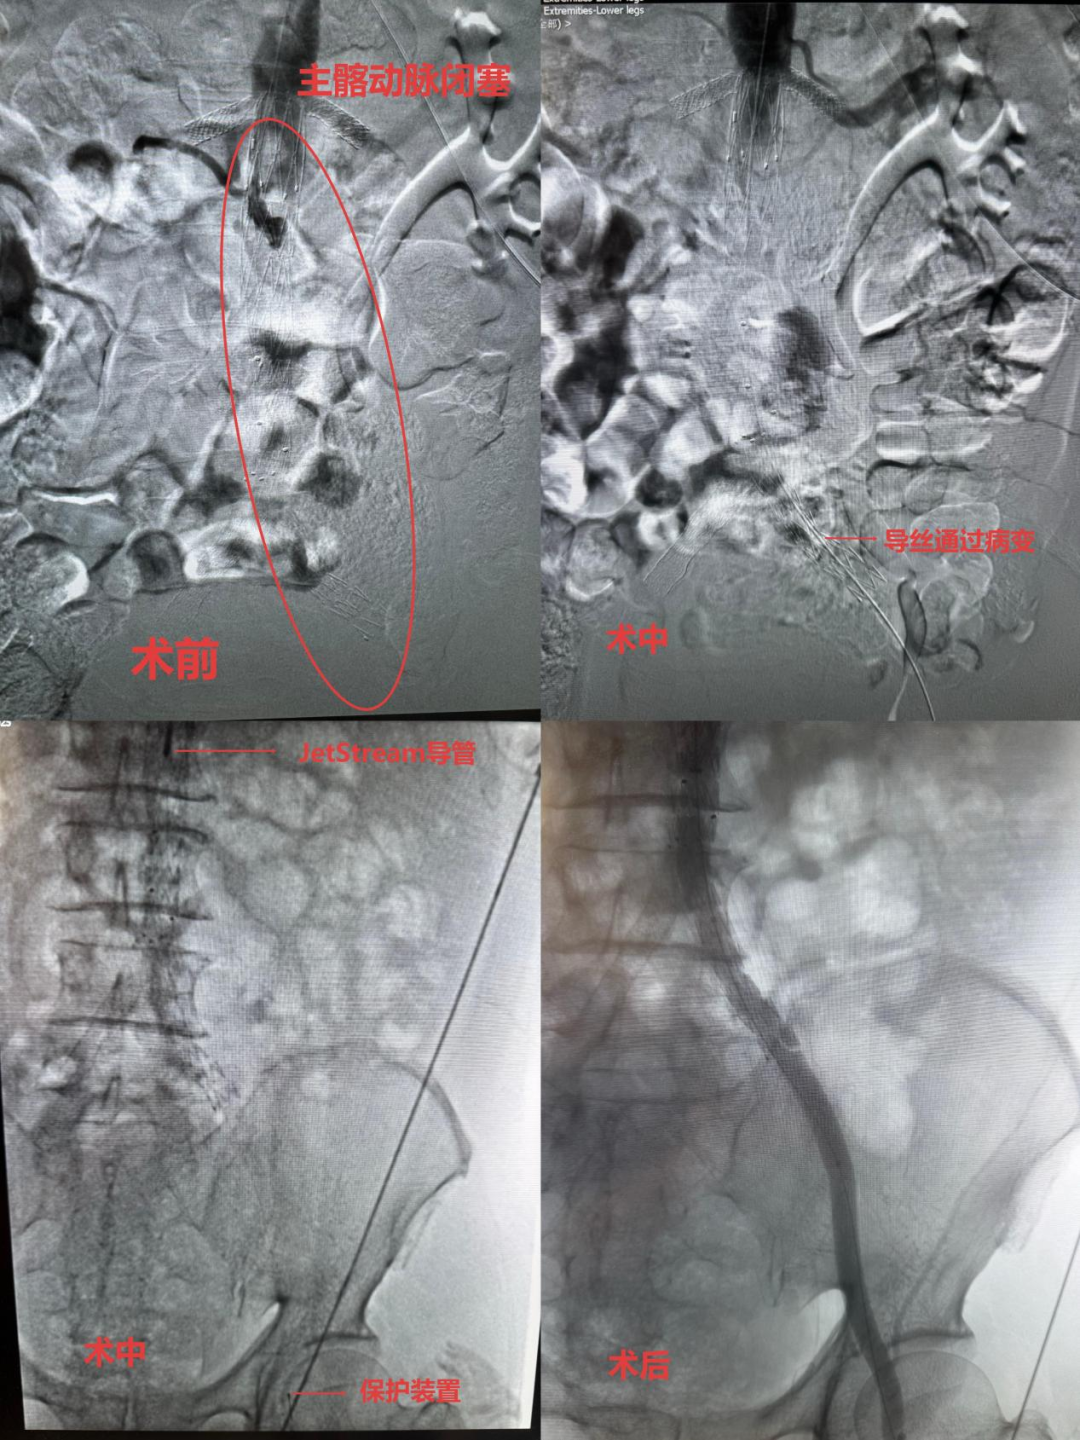

经CTA检查确诊患者为腹主动脉下段及双髂总动脉支架内闭塞,双髂外动脉起始段闭塞,左侧膝下动脉均为显影(考虑闭塞)。患者此前经过两次手术后,形成长段血管闭塞,常规治疗入路不可行,且抵触再次开放手术,左下肢可能面临截肢风险,生命受严重威胁。

该院血管介入科手术团队(马磊主任、王程阳副主任医师、李轶主治医师),反复研究术前影像与病变特点,经过充分的术前讨论和评估,决定经肱动脉入路在保护装置加持下采用最新的机械旋切抽吸(JetStream)技术施治,该技术已应用于下肢动脉病变治疗,但经肱动脉路径治疗主—髂动脉闭塞为首次运用,既规避常规入路局限,又契合患者微创需求。

手术中,该院血管介入科团队经患者肱动脉成功穿刺并置入鞘管,在DSA(数字减影血管造影)的精准引导下,导丝成功通过闭塞段,并置入保护装置,提前预防旋切后部分脱落碎屑造成的远端血管二次栓塞。再用JetStream导管送至闭塞部位,通过高速旋转的旋切、抽吸装置,高效、精准地清除硬化斑块和血栓。后续经左侧股动脉顺行穿刺,以AcoStream血栓抽吸导管对膝下动脉进行血栓清除治疗。

2个多小时的紧张操作,手术顺利完成,患者左下肢血管全程通畅,下肢缺血症状明显改善,为患者成功规避截肢的风险,同时避免了金属支架置入。